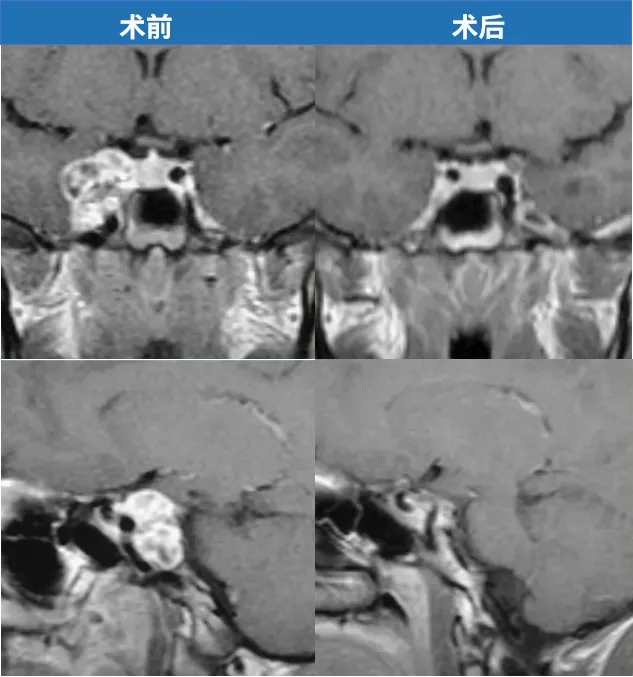

谜底在于肿瘤的精密位置。影像上可以看到它生长于控制眼动的第六颅神经与交感神经纤维之间。当时的物理治疗,实际上是破坏了这些交感神经躯干,意外地缓解了神经所受的压迫,没有了牵拉,斜视症状得以暂时消失。

这并非真正的治愈,而是以一种偶然的方式“掩盖”了问题。随着时间推移,脑膜瘤逐渐增大,最终直接压迫到第六颅神经,导致斜视再次出现,也终于暴露了它多年的潜伏。